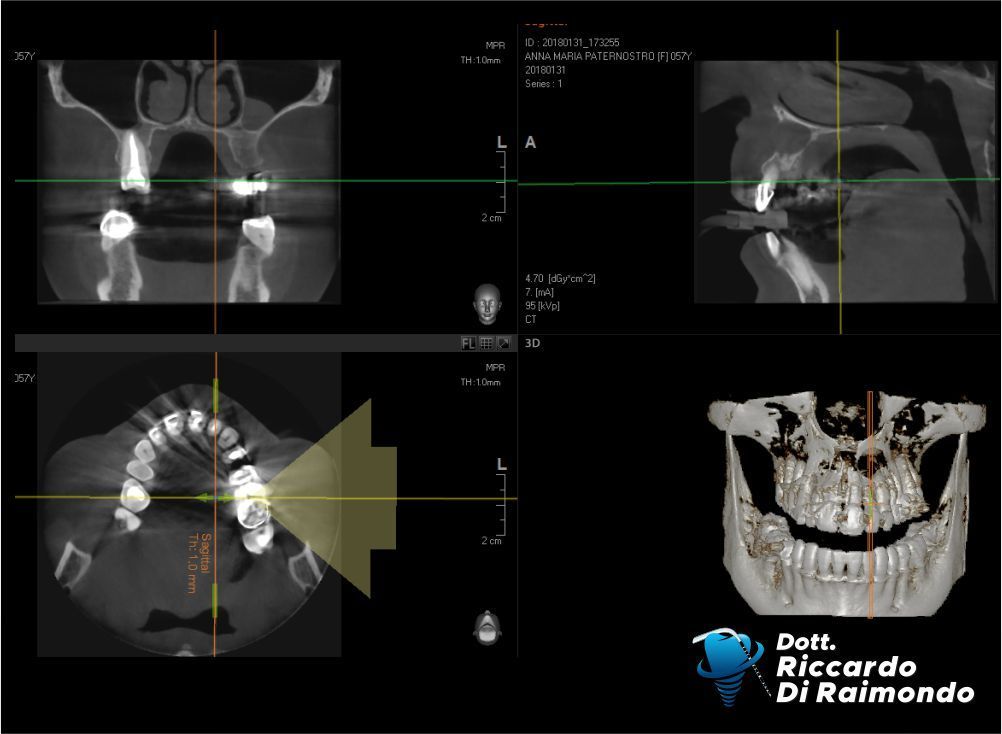

Rimozione cisti mascellare superiore frontale

Prima del Trattamento